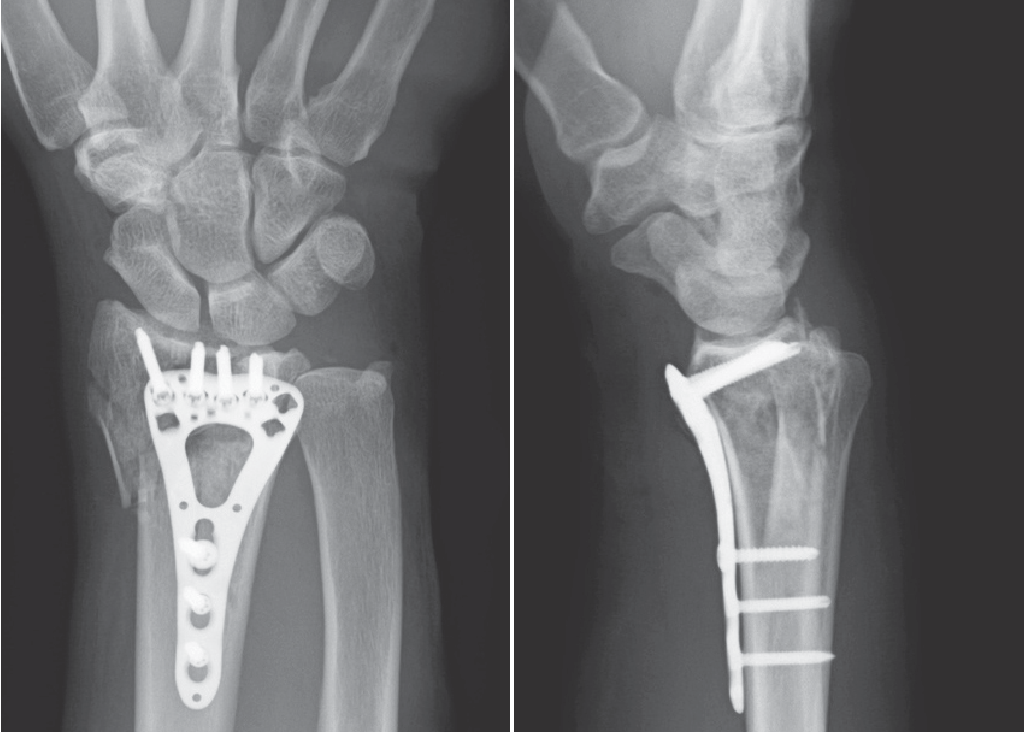

2023-07-06 В области ортопедической хирургии развитие и эволюция различных хирургических методов и устройств в значительной степени способствовали улучшению результатов лечения пациентов.Одним из таких достижений является фиксирующая пластина, специализированный ортопедический имплантат, используемый для фиксации переломов и деформаций костей.Чт